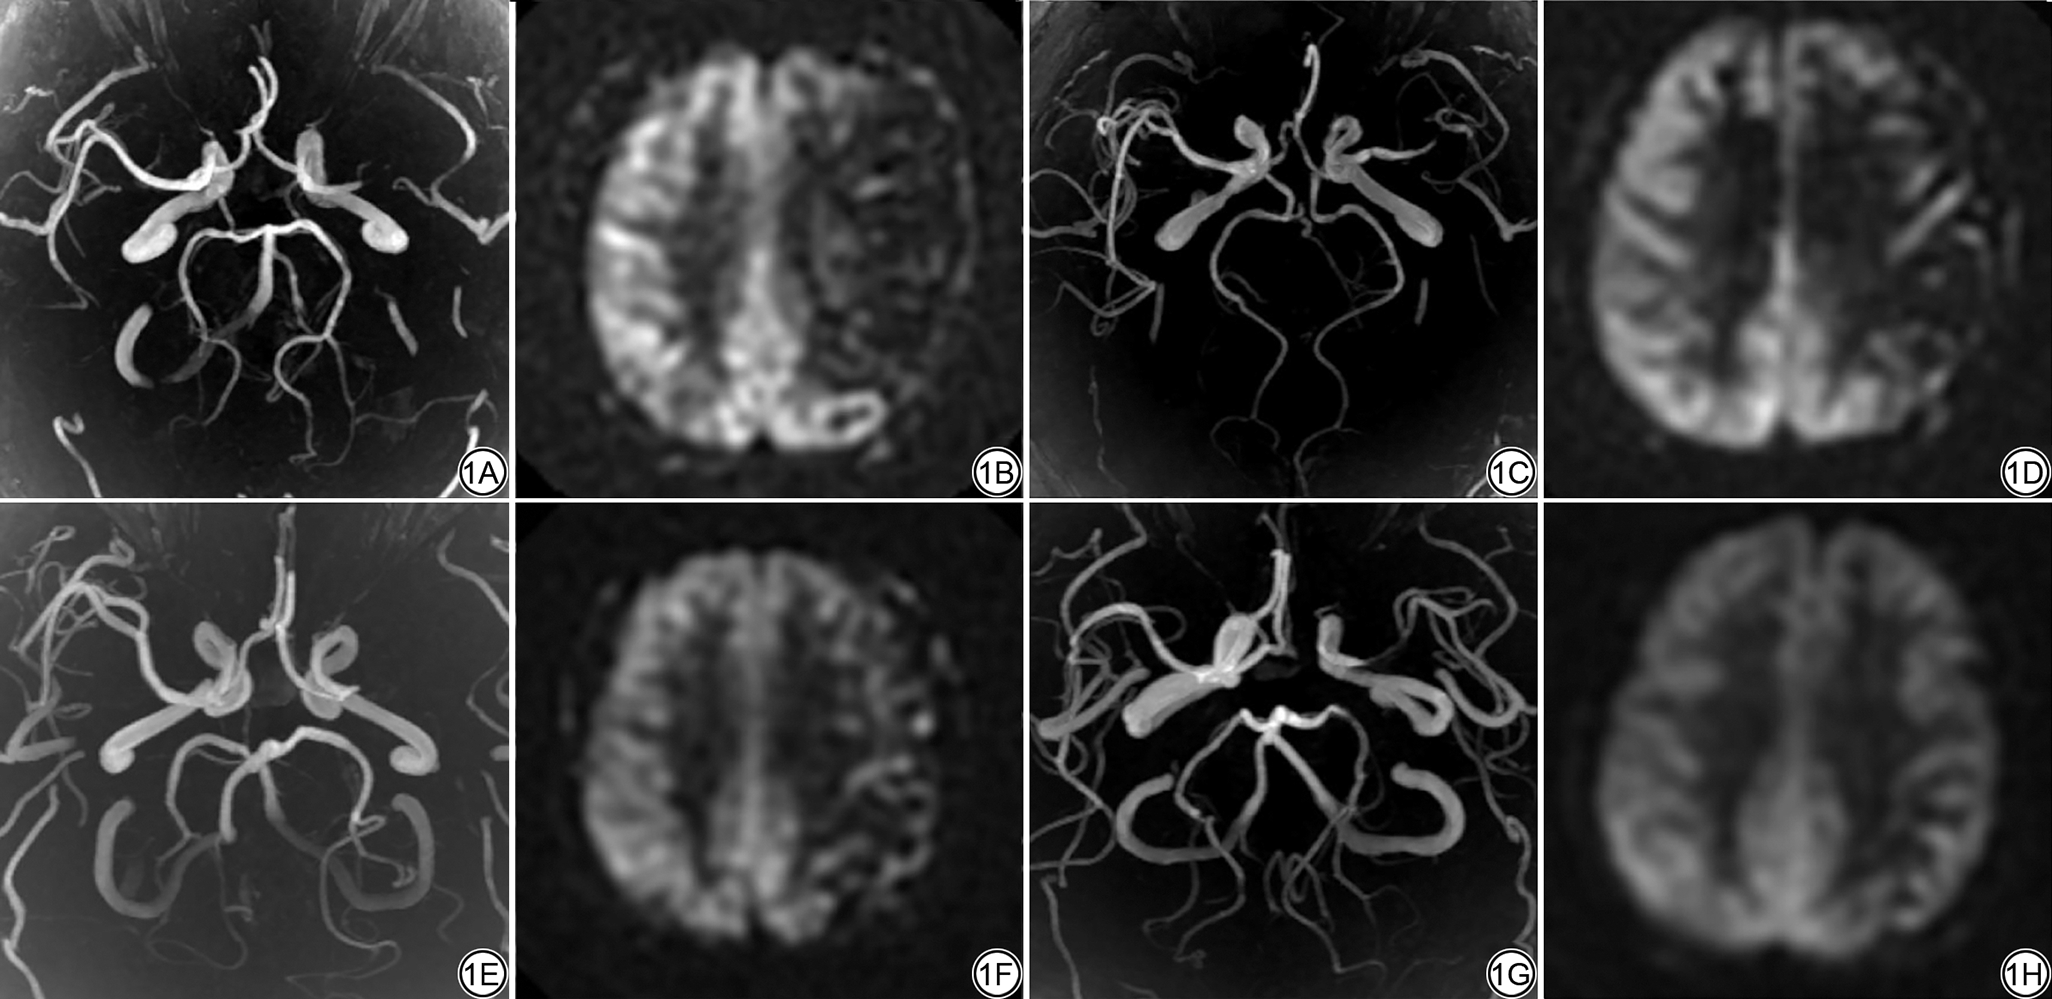

3D-pCASL评估侧支循环。在PLD为2525 ms的3D-pCASL图像上识别动脉穿行伪影(arterial transit artifact, ATA)并进行分组,依据是ATA信号范围。0级:异常灌注,缺血区无ATA;1级:ATA分布范围小于1/2缺血区;2级:ATA分布范围超过1/2缺血区;3级:正常灌注,无ATA。0级和1级为侧支循环不良,2级和3级为侧支循环良好[10]。见图1

图1  3D-pCASL评估侧支循环示意图。四例ICAS患者,左侧中动脉重度狭窄。1A~1B:男,45岁,侧支循环0级;1C~1D:男,66岁,侧支循环1级;1E~1F:女,43岁,侧支循环2级;1G~1H:男,40岁,侧支循环3级。1A、1C、1E、1F为MRA-MIP图;1B、1D、1F、1H为3D-pCASL原始图(PLD为2525 ms)。3D-pCASL:三维准连续动脉自旋标记;ICAS:动脉粥样硬化性狭窄;MRA-MIP:磁共振血管造最大密度投影;PLD:标记后延迟时间。

Fig. 1  Schematic diagram of collateral circulation assessment using 3D-pCASL. Four ICAS patients with severe stenosis of the left middle cerebral artery. 1A-1B: Male, 45-year-old, grade 0; 1C-1D: Male, 66-year-old, grade 1; 1E-1F: Female, 43-year-old, grade 2; 1G-1H: Male, 40-year-old, grade 3. 1A, 1C, 1E, 1F: MRA-MIP; 1B, 1D, 1F, 1H: 3D-pCASL raw images (PLD = 2525 ms). 3D-pCASL:three-dimensional pseudo-continuous arterial spin labeling; ICAS: intracranial atherosclerotic stenosis; MRA-MIP: magnetic resonance angiography - maximum intensity projection; PLD: post labeling delay.